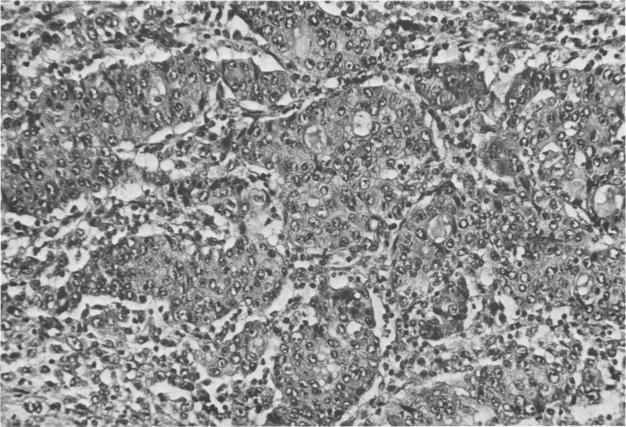

Three patients with mucoepidermoid carcinoma of the bile duct are described. In two patients the tumor arose from the common hepatic duct. Mucoepidermoid carcinoma of the extrahepatic bile duct has not been previously reported. The clinical features and pathologic behavior of this rare type of tumor are similar to the usual biliary adenocarcinoma. The coexistence of Clonorchis sinensis infestation and primary pyogenic cholangitis raises the possibility of an etiologic association.

本文描述了3例胆管黏液表皮样癌患者。其中2例肿瘤起源于肝总管。肝外胆管黏液表皮样癌此前未见报道。这种罕见类型肿瘤的临床特征和病理行为与常见的胆管腺癌相似。华支睾吸虫感染与原发性化脓性胆管炎并存增加了病因学关联的可能性。